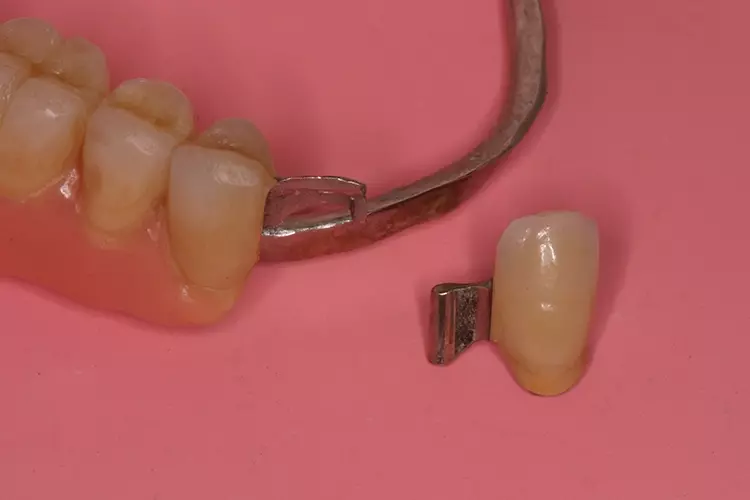

Als relative Kontraindikation sind karies- und restaurationsfreie Pfeilerzähne mit zervikalen keilförmigen Defekten über 1 mm Tiefe zu nennen, da diese zu einer erhöhten Frakturgefahr des Pfeilerzahnes bei Belastung führen. Adhäsivattachments können zur Reparatur vorhandener Doppelkronen- oder Geschiebearbeiten verwendet werden, sofern der verbliebene Nachbarzahn einer verloren gegangenen Doppelkrone karies- und restaurationsfrei ist. Die Matrize wird in diesem Fall in die ausgeschliffene Doppelkrone oder in die Geschiebekrone des verlorenen Pfeilerzahns eingeklebt (Abb. 1 bis 4).

Adhäsivattachments werden in der Regel aus Cobalt-Chrom(CoCr)-Legierungen hergestellt. Um eine ausreichende Steifigkeit des Materials zu gewährleisten, sollte eine Mindeststärke des Adhäsivflügels von 0,7 mm eingehalten werden. Die Ränder sollten möglichst auf Minimalstärke ausgearbeitet werden.

Die Klebefläche sollte mindestens 30 mm2 betragen. Empfohlen werden kostengünstige extrakoronale, semipräzise Stabgeschiebe mit auswechselbaren Kunststoffmatrizen (z.B. Preci-Vertix, Fa. Ceka, Hannover). Um Frakturen zu vermeiden, sollten die Geschiebestäbe extrakoronal mit einer Mindestverbinderhöhe von 3 mm zwischen Stabgeschiebe und Adhäsivflügel konstruiert werden. Die auf 3 mm kürzbaren Geschiebestäbe sollten parodontalfreundlich mit einer Führung für Interdentalraumbürstchen durch eine direkte, ponticförmige Auflage auf dem Kieferkamm angebracht werden.